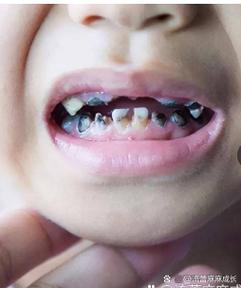

生活习惯和饮食因素对门牙蛀牙的影响也不容忽视,现代饮食中,高糖食物和酸性饮料的摄入量增加,如碳酸饮料、果汁、糖果、糕点等,这些食物不仅含有大量糖分,其酸性也会直接腐蚀牙釉质,门牙作为切割食物的主要牙齿,在进食时首先接触这些食物,更容易受到直接攻击,频繁饮用碳酸饮料而不及时漱口或清洁,会导致牙釉质表面被酸蚀,变得粗糙,更容易附着细菌和食物残渣,不良的口腔卫生习惯,如刷牙次数不足、刷牙方法不正确(如未采用巴氏刷牙法,遗漏牙面)、不使用牙线清洁邻面等,都会导致牙菌斑和牙结石堆积,为细菌提供了繁殖的温床,对于儿童来说,门牙蛀牙还可能与“奶瓶龋”有关,即长时间含着奶瓶或母乳入睡,牛奶中的乳糖在口腔中被细菌分解,产生酸性物质,腐蚀门牙。

问:儿童门牙蛀牙(奶瓶龋)需要治疗吗?

答:儿童门牙蛀牙(奶瓶龋)必须及时治疗,乳牙虽然会被恒牙替换,但乳牙的健康对恒牙的发育、颌骨的生长以及儿童的咀嚼、发音和心理发育都有重要影响,奶瓶龋进展迅速,容易导致乳牙牙冠大面积破坏,引发疼痛、感染,甚至影响下方恒牙胚的发育,治疗方法包括涂氟、补牙、根管治疗等,具体需根据龋坏程度由医生决定,家长应注意纠正儿童含奶瓶入睡的习惯,饭后漱口,并尽早开始口腔清洁,帮助儿童养成良好的口腔卫生习惯。